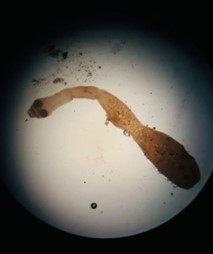

CONCURSO FOTOGRÁFICO

En el cierre de las XL Jornadas Nacionales de Hidatidología, realizadas en Trelew, en noviembre de 2025, se entregaron los premios a las mejores fotografías aportadas por los miembros de la Asociación de Hidatidosis Argentina, Filial de la Asociación Internacional de Hidatidología.

En el PDF … las dos fotos más votadas de cada categoría: Estadio parasitario, trabajo en Laboratorio, trabajo en Terreno, el nombre de sus autores y la descripción de cada foto.